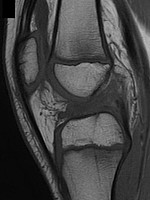

Figura 3: Lesione di LCA in paziente di 14 con fisi aperte (a) e Risonanza magnetica di controllo a 2 anni di follo-wup dopo ricostruzione del LCA con tecnica over-the-top sovra-fisaria